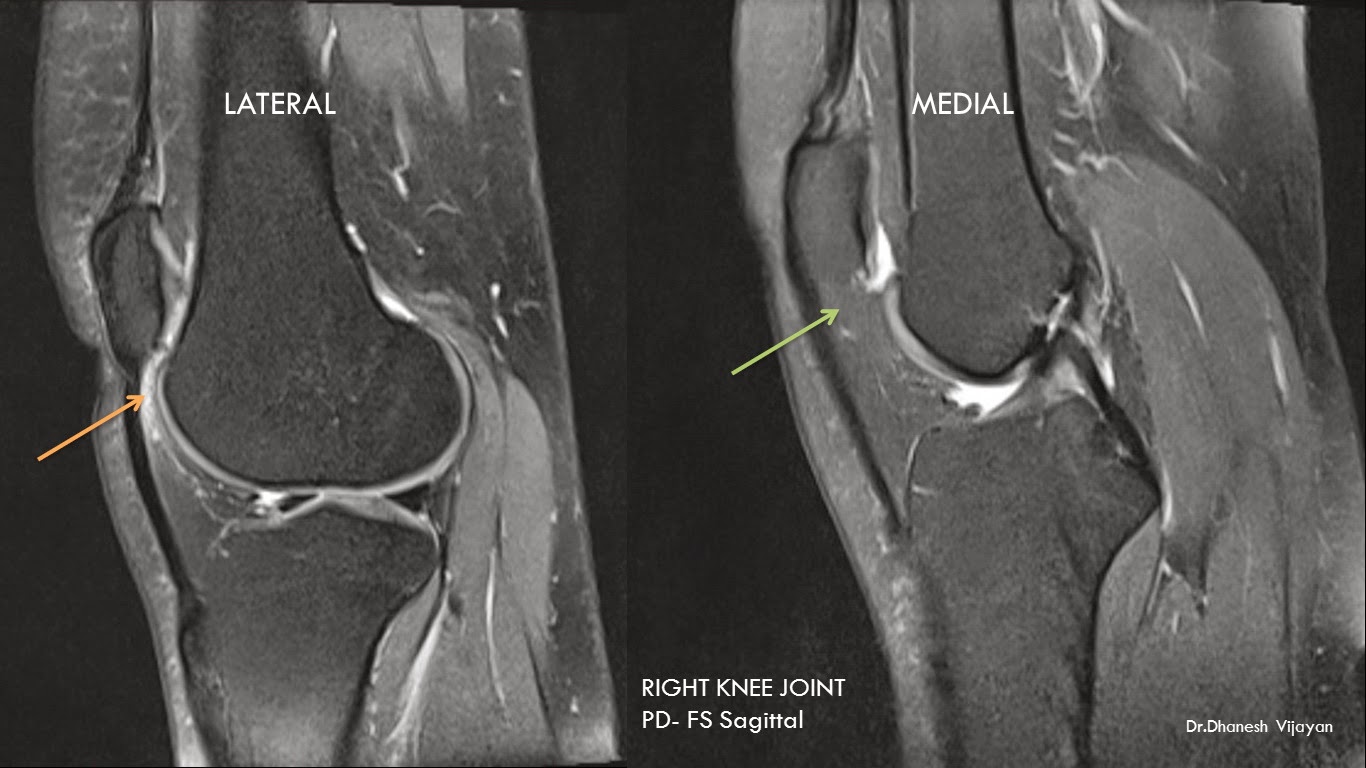

Супрапателлярный импиджмент коленного сустава: симптомы и лечение